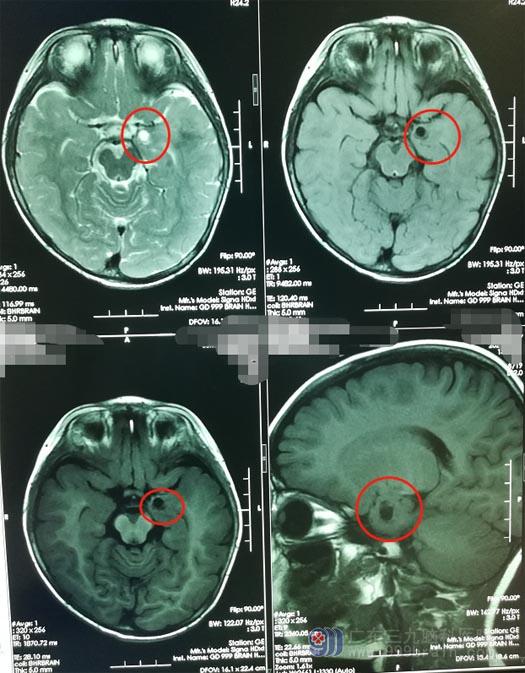

刚好有认识的亲戚曾在广东三九脑科医院神经外五科做过手术,他极力地推荐他们也去看一下。心急如焚的小雪父母听从了亲戚的建议。主治医生林德留安排小雪做了脑部的相关检查,MR结果显示颞叶内侧有一囊性占位病变,ASL低灌注表现,MRS显示很可能是一个低级别胶质瘤。

小雪是“幸运”的,无意中摔了一跤,在肿瘤还没有长大和进一步恶化的时候就被及时发现。颞叶内侧低级别胶质瘤广泛性切除是可取的, 术后进行定期影像学观察, 一般是不会复发。